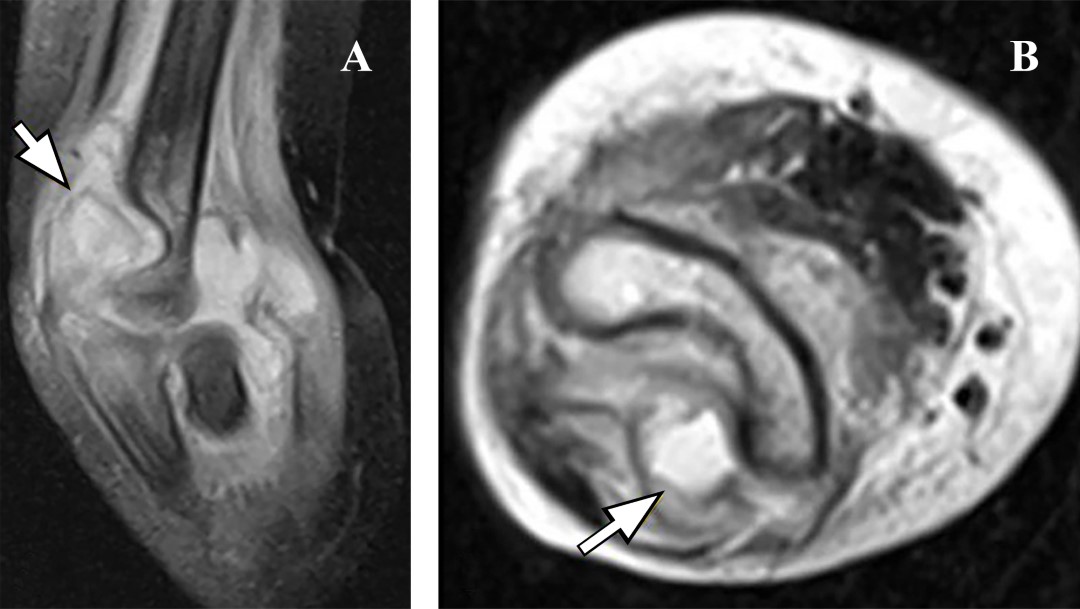

Figura 2